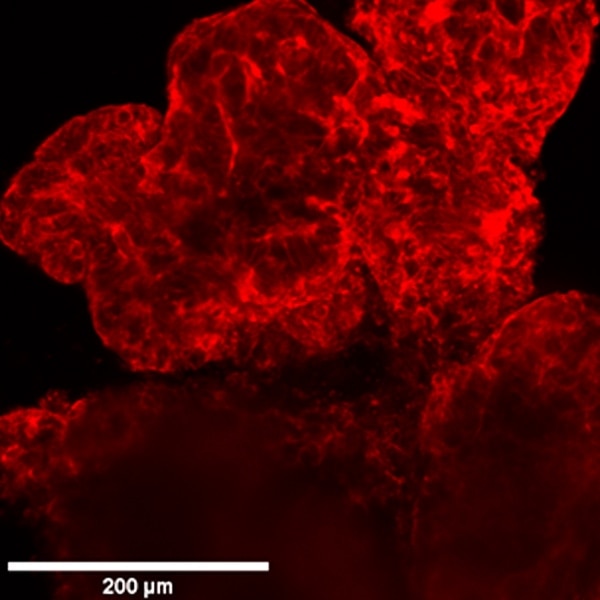

Here are shown organoids cultured in Matrigel on optical multi-well plates and generated from primary stem cells from colon cancer biopsies and stained for cytoskeleton by Phalloidin-568.

Comparison between Widefield, Confocal Spinning Disk and Super Resolution acquisitions.

Video Confocal Super-resolution (VCS)